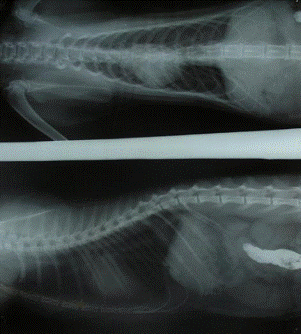

На рентгеновском снимке было выявлено: нарушение

очертаний диафрагмы с увеличением плотности мягких тканей внутри грудной

клетки, смещение сердца в краниальном направлении, а так же наполненные газом

кишечные петли и газовый пузырь желудка, смещённые в грудную полость.

Пролабированные органы брюшной полости ограничиваются овальной тенью грыжевого

мешка. Локализация выпяченного участка диафрагмы соответствует области купола

диафрагмы.

Рис. 1.Нарушение очертаний диафрагмы,

пролабирование органов в грудную полость.

Диагноз был установлен на основании анамнеза,

клинических признаков, результатов рентгенографии (Нарушение очертаний

диафрагмы с увеличением плотности мягких тканей внутри грудной клетки, смещение

сердца в краниальном направлении, наполненные газом кишечные петли и газовый

пузырь желудка, смещённые в грудную полость, ограничение пролабированных

органов брюшной полости овальной тенью грыжевого мешка. Локализация выпяченного

участка диафрагмы соответствует области купола диафрагмы.) и гастроэндоскопии